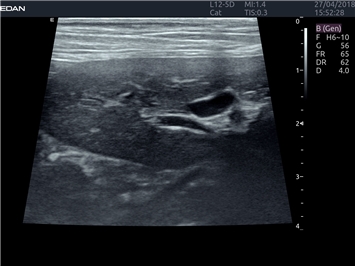

EDAN Acclarix LX4 VET

EDAN Acclarix LX4 VET представляет собой профессиональную ультразвуковую систему, специально разработанную для ветеринарных исследований. Сочетание стабильности, высокой производительности и эффективности делает эту систему идеальным выбором для современной ветеринарной практики.

• Универсальные датчики для различных видов животных

• Специализированные предустановки для ветеринарных исследований

• Гибкие протоколы исследований